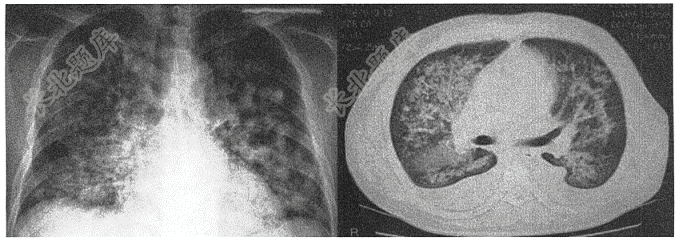

- 单项选择题老年患者,因反复胸闷、气促2年,加重伴痰中带血1天入院,体查:双肺可闻及大量湿啰音,心率120次/分。既往有冠心病病史。肺部影像如图,结合患者病史最可能诊断是( )

A、粟粒性肺结核

B、急性肺水肿

C、肺转移癌

D、肺炎

E、过敏性肺炎